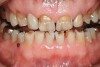

Figure 1   Classic presentation of the bruxism triad. Lateral wear pattern, generalized buccal tooth loss from erosion and abrasion, and history of sleep disruption.

Figure 1

Tooth wear is described in the literature as the loss of the constitution of the tooth and has been classified as being caused by attrition, abrasion, erosion, or a combination of these factors.9 As it relates to SB, tooth wear is reported to additionally cause tooth mobility, temperature hypersensitivity, and tooth fracture.10 While sleep bruxers and non-bruxers displayed significantly different amounts of wear over time, the contribution of tooth-on-tooth attrition to this wear is still controversial.11 It has been postulated that much of the wear could be erosion rather than attrition. Interestingly, those two factors are interwoven in the bruxism triad patient, magnifying the wear in this patient population (Figure 1).